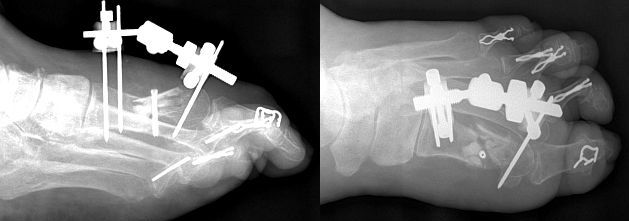

Query: Comminuted Fracture S/P Surgery

This 53 y/o female presented with an S/P ORIF comminuted fracture of the first metatarsal of the right foot w/ex fix application. The patient walked on the osteotomy site which caused the fracture and implant dislocations.

Comminuted Fracture 1st Metatarsal S/P Surgery |

The patient reports bumping her surgical foot against a doorpost while stumbling in the dark. X-rays show a dorsal shift in the capital fragment. The patient has proven to be quite difficult. I'm concerned, to say the least. Any suggestions will be greatly appreciated.

Name Withheld